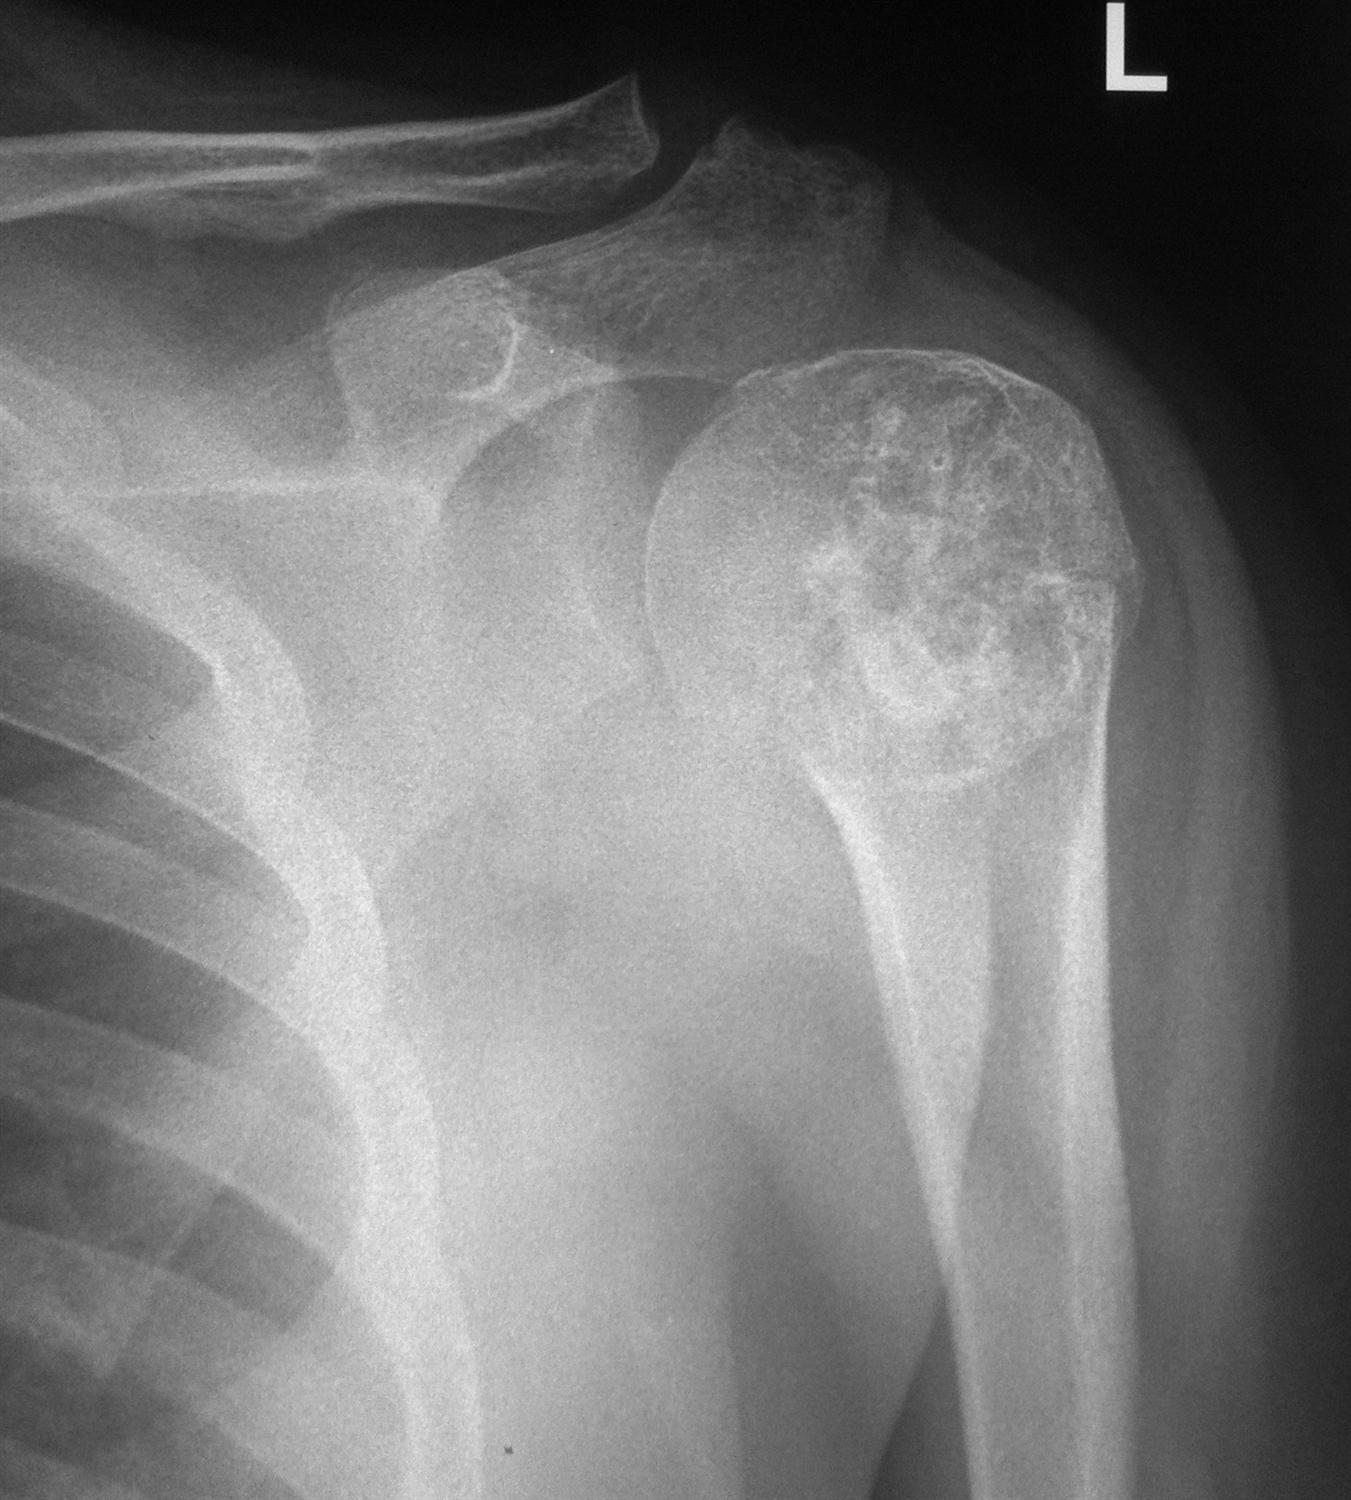

From www.tumorsurgery.org

Enchondroma Benign Bone Tumor Tumors of Bone Malignant Neoplasm Of Shoulder Soft tissue sarcoma is a type of cancerous tumor that forms in the soft tissues of the body, such as muscle, fat, fibrous tissue, and blood vessels. The musculoskeletal tumor society has developed a classification system for shoulder girdle tumors that divides the scapula into two zones : The surgical treatment of a malignant bony tumor involving the shoulder girdle. Malignant Neoplasm Of Shoulder.